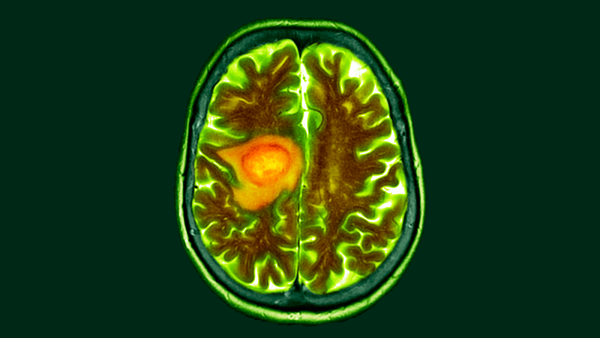

Дослідники вивчають потенціал золотих наночастинок (жовтих цяток) для доставки ліків в організм. (Зображення: Вероніка Сапожнікова, Костянтин Соколов, Ребекка Річардс-Кортум/MD Anderson Cancer Center and Rice University через NIH/Flickr)

Наночастинки — жовті цятки — можна розробити так, щоб вони націлювалися на ракові клітини, які мають синій колір.